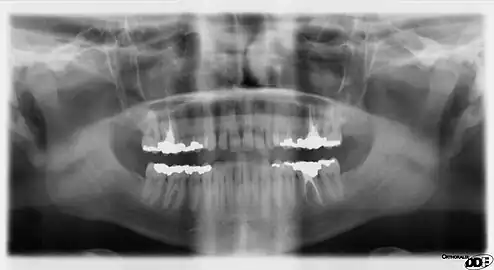

Panoramic films

Panoramic films are extraoral films, in which the film is exposed while outside the patient's mouth, and they were developed by the United States Army as a quick way to get an overall view of a soldier's oral health. Exposing eighteen films per soldier was very time consuming, and it was felt that a single panoramic film could speed up the process of examining and assessing the dental health of the soldiers; as soldiers with toothache were incapacitated from duty. It was later discovered that while panoramic films can prove very useful in detecting and localizing mandibular fractures and other pathologic entities of the mandible, they were not very good at assessing periodontal bone loss or tooth decay.[18]